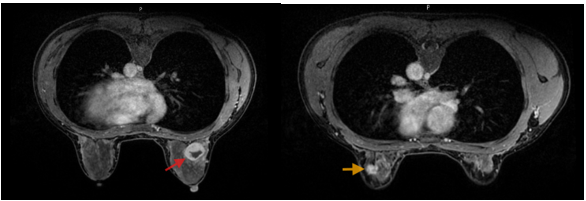

- Chụp cộng hưởng từ tuyến vú: Hình ảnh tổn thương vú trái (phân loại BIRADS 4C). Tổn thương dạng nang phức hợp vú phải (phân loại BIRADS 4A).

Hình 2. Hình ảnh MRI: Vú phải: Vị trí khoảng 11h, cách núm vú 35mm, có tổn thương dạng nang phức hợp kích thước 26x25x27mm, bờ đều ranh giới rõ, thành dày không đều và ngấm thuốc sau tiêm - BIRADs 4A (mũi tên đỏ). Vú trái: Vị trí khoảng 1h, cách núm vú 45mm có nốt tổn thương kích thước 18x13x9mm, bờ tua gai, co kéo nhẹ nhu mô tuyến vú lân cận; không thấy xâm lấn da và thành ngực - BIRADs 4C (mũi tên vàng).